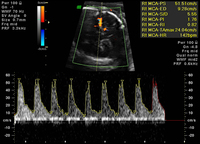

Aumento de la velocidad en la arteria cerebral media, coherente con anemia fetal grave

Ottawa Hospital; utilizado con el consentimiento de la paciente